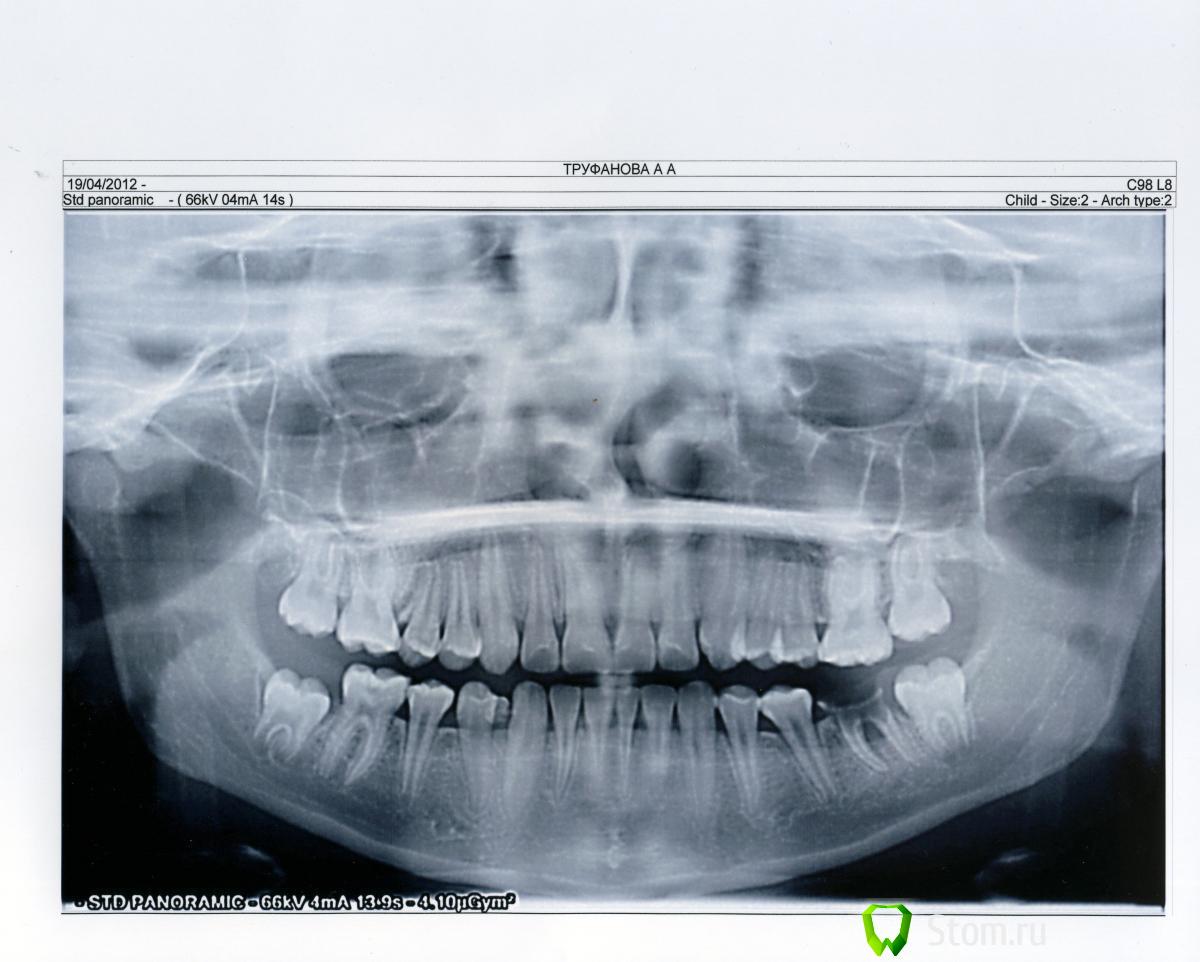

Елена Архипова Опубликовано 23 апреля, 2012 Поделиться Опубликовано 23 апреля, 2012 Здравствуйте! У меня вопрос к Bier. Ребенку 13 лет, 6 зуб слева разрушен. Вопрос: что с ним можно сделать? Удалить или можно попробовать восстановить (мб культевая вкладка?) А в случае удаления надо ставить имплант? Снимок отправила на адрес oconnor@stom.ru. Очень надеюсь на вашу помощь Ссылка на комментарий

Bier Опубликовано 24 апреля, 2012 Поделиться Опубликовано 24 апреля, 2012 зуб однозначно на удаление и к ортодонту. С ним решать вопросы: 1. удержание 26 зуба от смещения вниз (он уже сместился немного) 2. Смещение 7го на место 6го или удержание места между 5м и 7м для последующей имплантации. Ссылка на комментарий

Doc Опубликовано 24 апреля, 2012 Поделиться Опубликовано 24 апреля, 2012 Хоть сейчас и модно ставить имплантаты в раннем возрасте, но по классике не раньше 18 лет. Так что зуб удалять, ортодонт держит пространство минимум до 16 лет, а лучше до совершеннолетия, тогда уже имплантация. Ссылка на комментарий